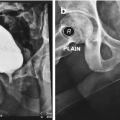

Metoidioplasty technique (combined graft and flap urethroplasty). (a) Preoperative appearance . Clitoris is hormonally enlarged; (b) The short urethral plate is divided, creating a gap. This maneuver is necessary to straighten and lengthen the clitoris. Buccal mucosa graft is placed and quilted to cover the gap. Flap is harvested from the right labia minora, to be joined with buccal mucosa graft; (c) Bulbar part of the neourethra is formed by joining the periurethral tissue and the proximal part of the urethral plate. The right labia minora flap is joined with a buccal mucosa graft to create the penile neourethra. Distal part of the urethral plate is tubularized creating the distal neourethra; (d) Appearance after metoidioplasty. Two testicular implants are inserted into the scrotum created from both labia majora

Metoidioplasty technique (urethral plate tubularisation). (a) Preoperative appearance. Urethral plate is wide and well developed; (b) Bulbar urethra is created using a well-vascularized vaginal flap and proximal urethral plate; (c) Urethral plate is tubularized to create penile and glandial neourethra. Proximal neourethra is covered with surrounding tissue to prevent postoperative fistula; (d) Outcome after metoidioplasty. Scrotum is formed by joining labia majora, and testicular implants are placed